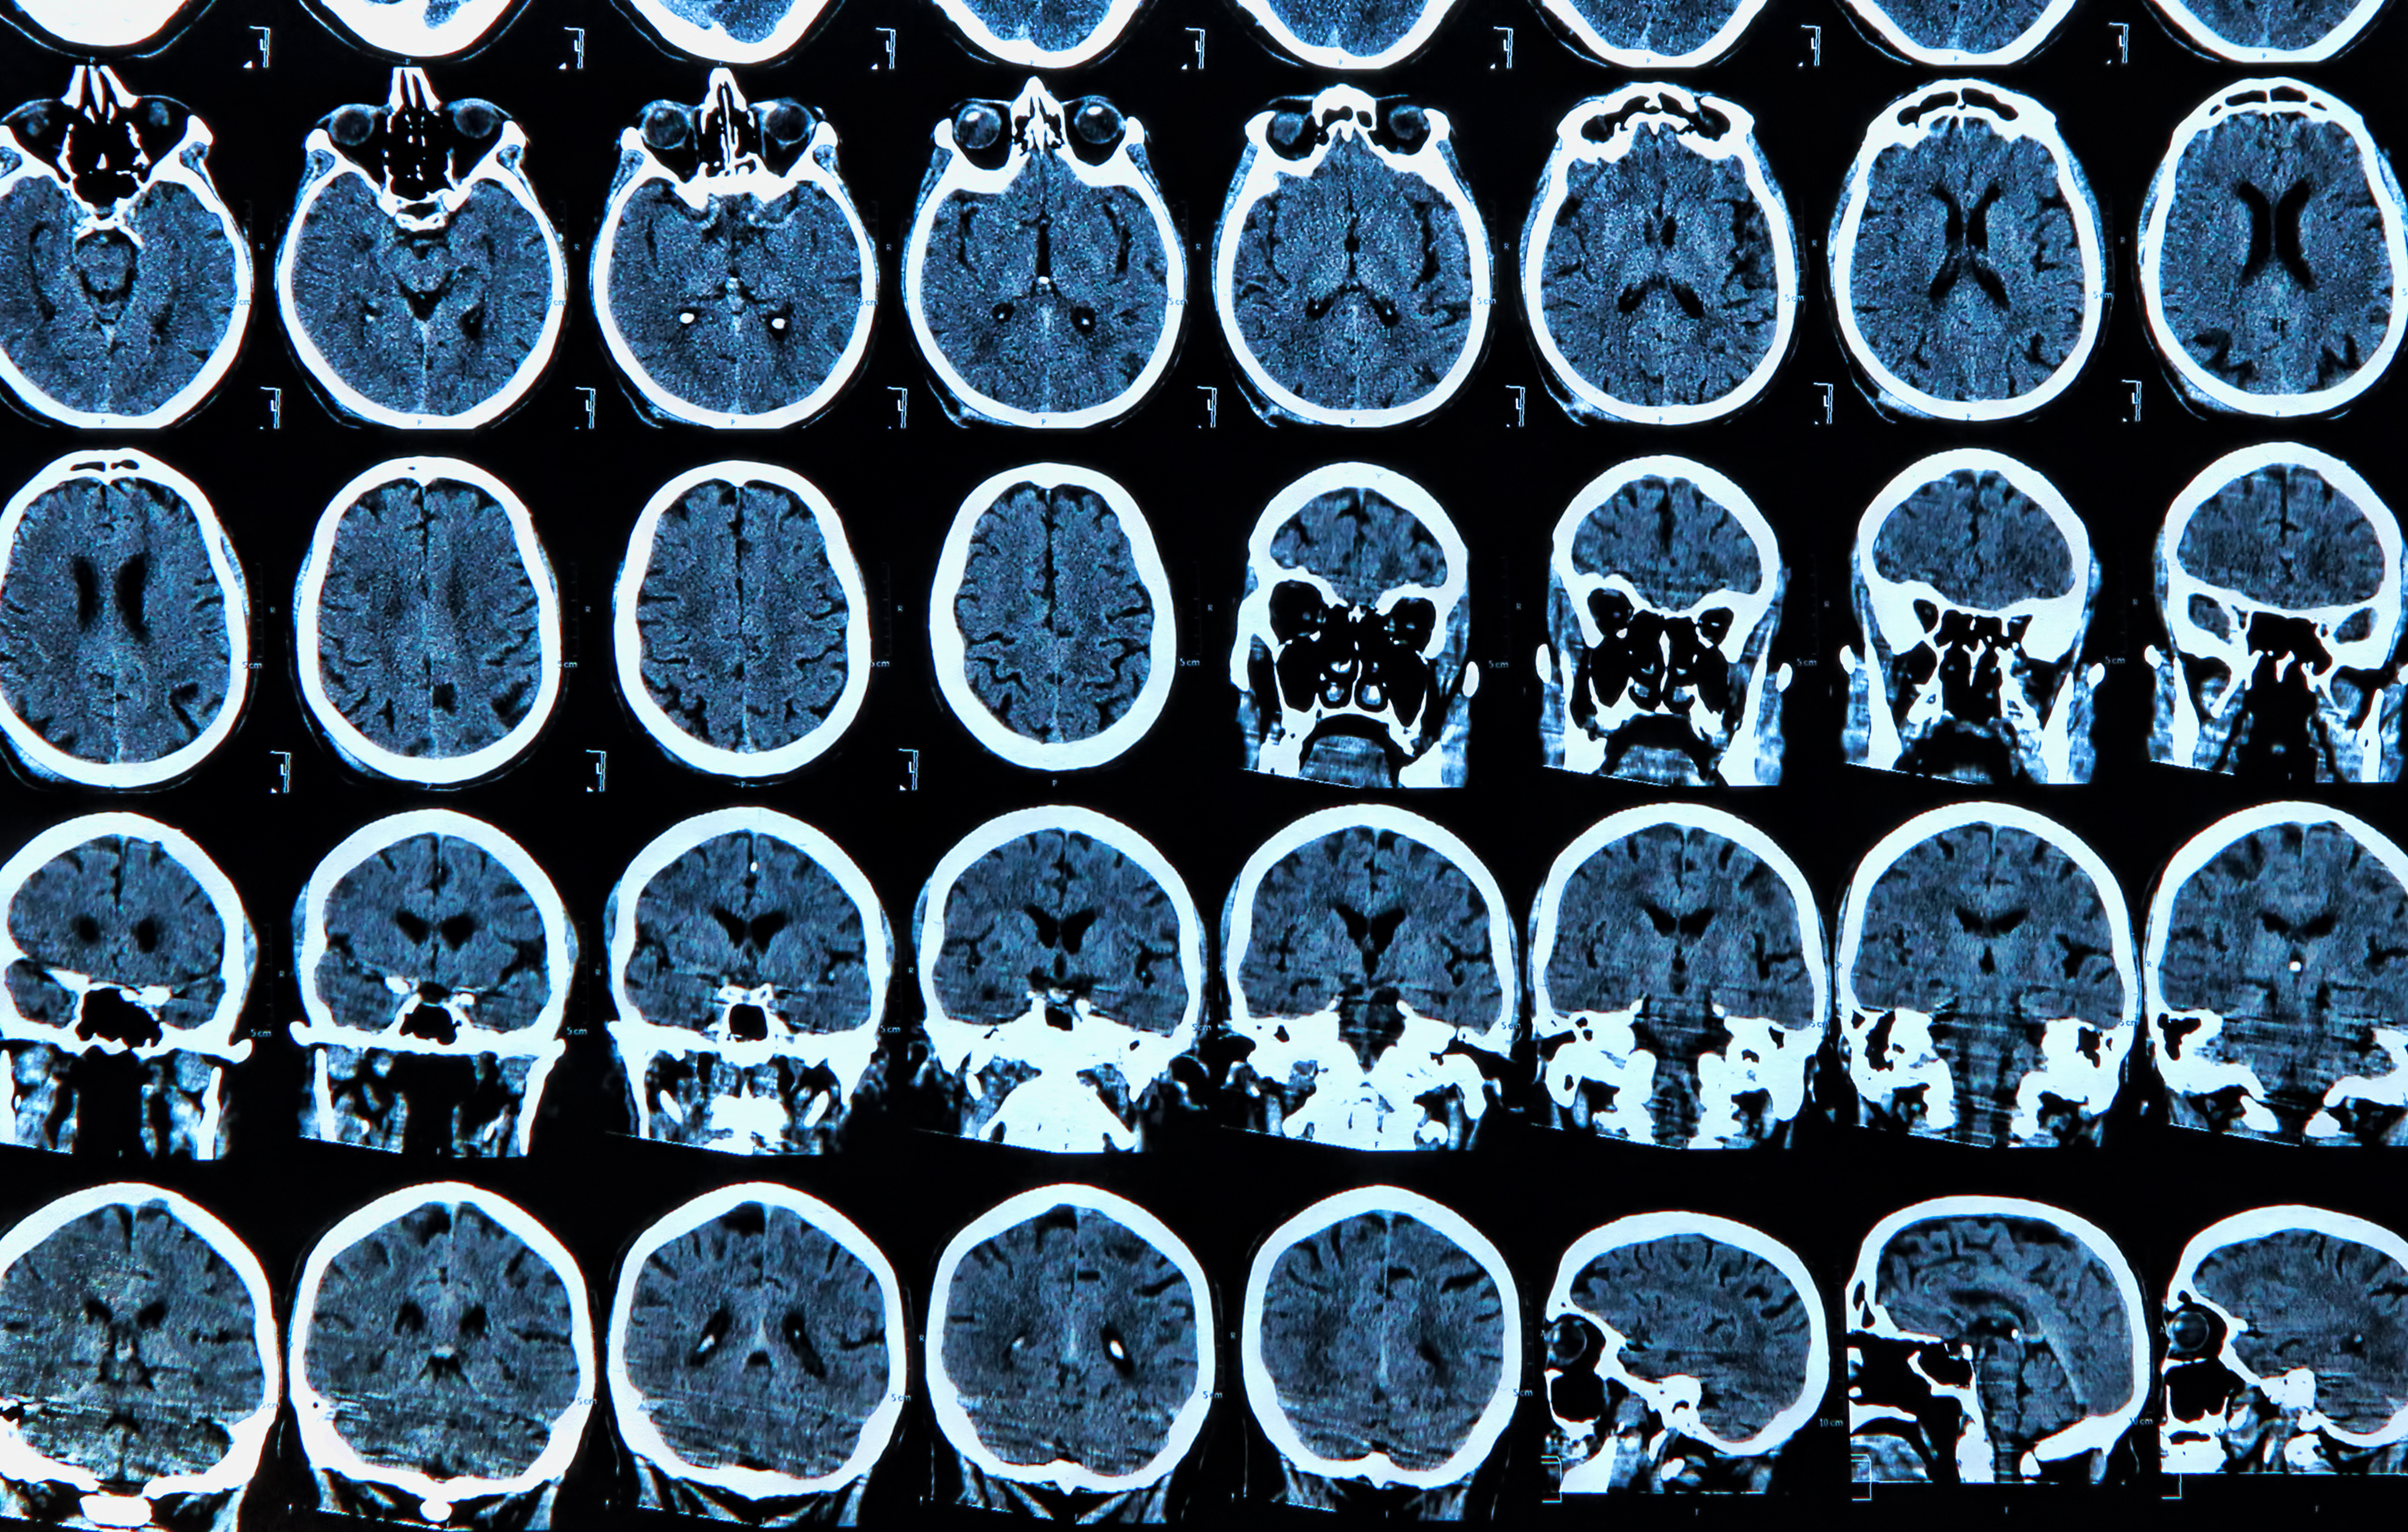

New research suggests that an emerging predictive biomarker, derived from a combination of magnetic resonance imaging (MRI) brain scans and a machine learning algorithm, has significantly greater accuracy than previously established measurements for diagnosing Alzheimer’s disease.